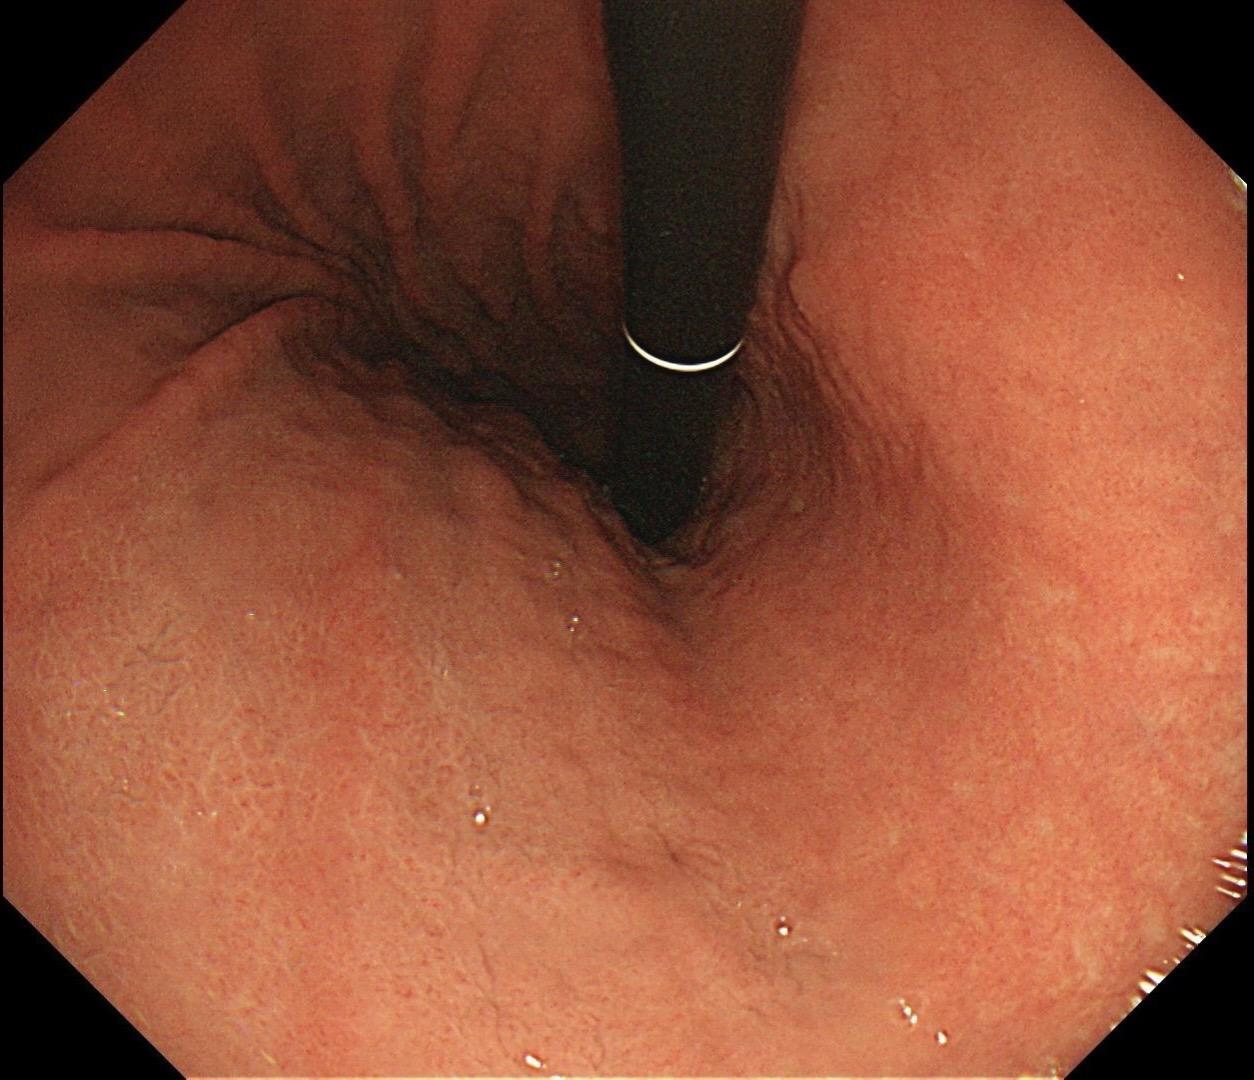

男,40岁,胃双发褪色调病变。慢性胃炎复查,3年前胃镜未见异常,Hp阳性背景,萎缩不明显,胃体下部大弯见一褪色调病变,浅凹陷,5mm左右,换用放大内镜观察,表面结构缺失,血管异型明显,未分化可能性大……胃窦后壁见一白斑,无高度差,NBI浅茶色,放大草草看了下,似有边界,IP增宽,活检待病理……小哥哥胖得几乎没脖子,腹式呼吸太明显~😖